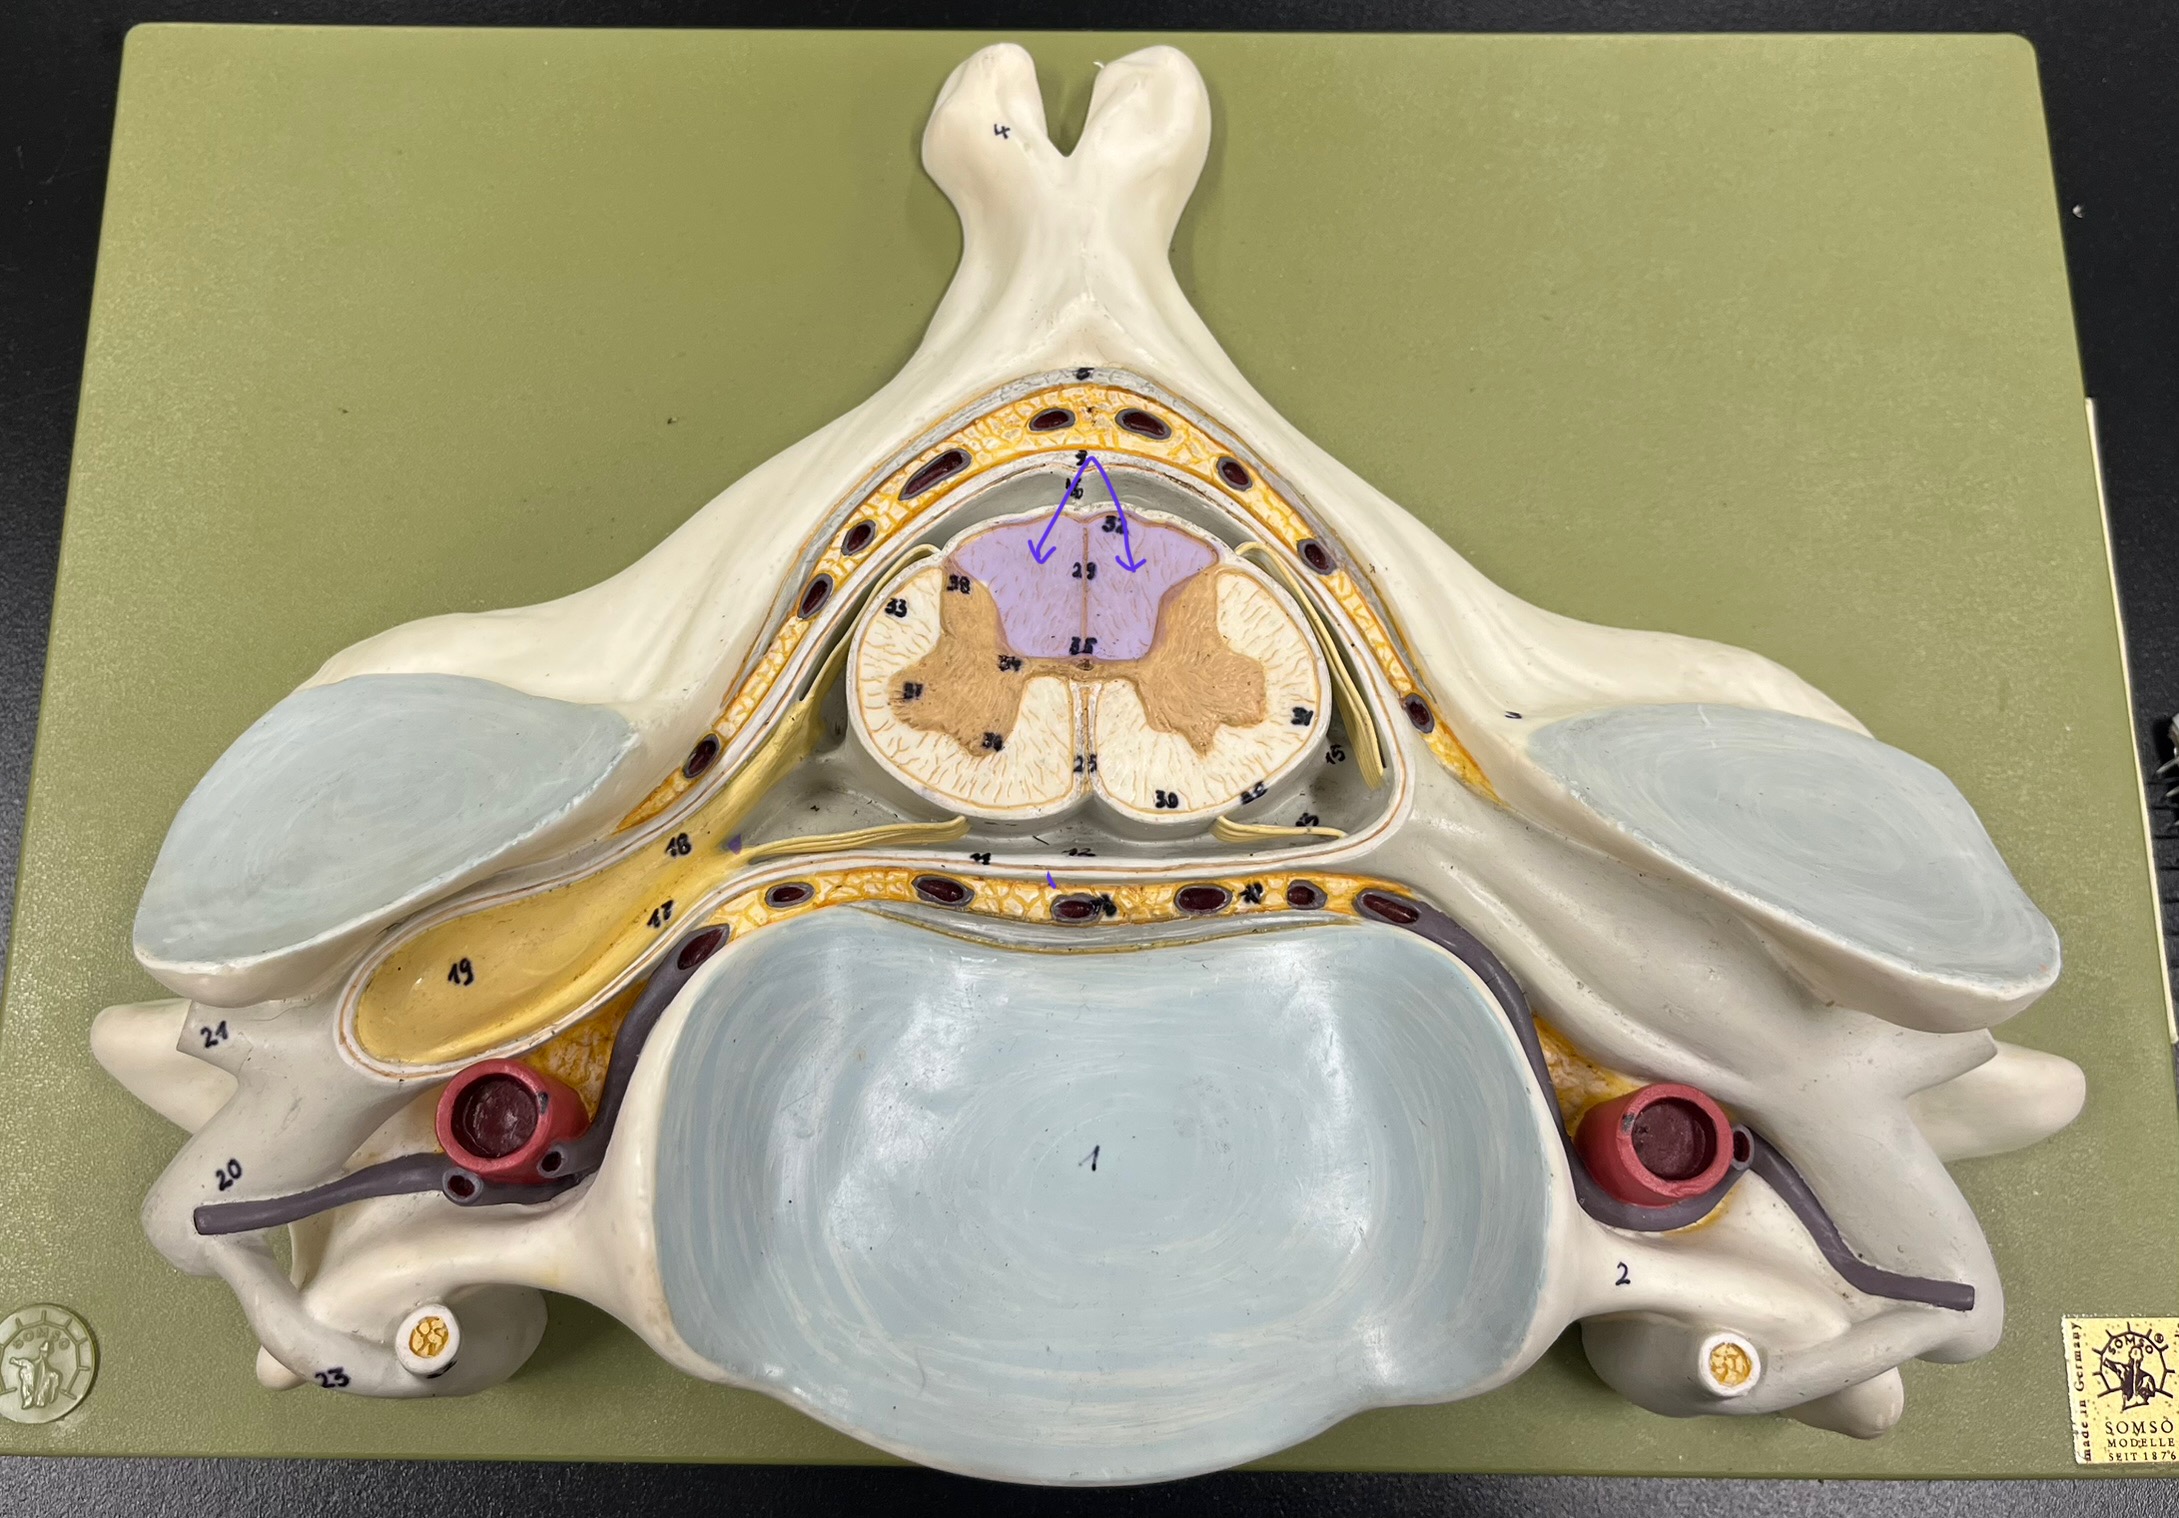

epidural space

dura mater

subdural space

arachnoid mater

subarachnoid space

pia mater

denticulate ligaments

What is the groove here?

anterior median fissure

posterior median sulcus

posterior (dorsal) horn

posterior (dorsal) horn; R—>L

anterior (ventral) horn

lateral horn (selected models)

gray commissure

central canal

anterior column

lateral column

posterior column

white commissure

posterior (dorsal) root ganglion

What is the bulb here?

posterior (dorsal) root ganglion

posterior (dorsal) root

posterior (dorsal) root

anterior (ventral) root

anterior (ventral) root

dorsal ramus

dorsal ramus

ventral ramus

ventral ramus

rami communicantes

rami communicantes

sympathetic chain ganglia

sympathetic chain ganglia